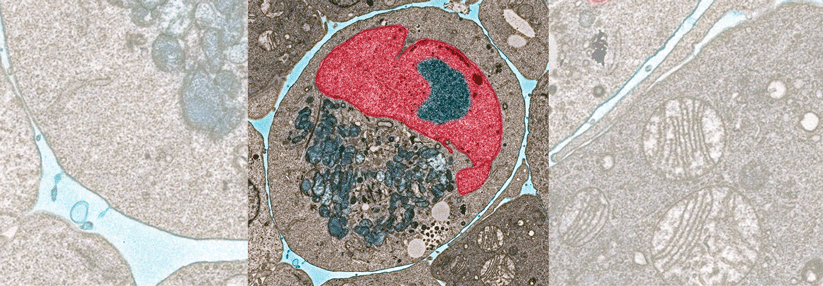

Quadruplet-Regime erzielen bei Patient:innen mit neu dia­gnostiziertem Multiplem Myelom MRD-Negativitätsraten. Quadruplet-Regime erzielen bei Patient:innen mit neu dia­gnostiziertem Multiplem Myelom MRD-Negativitätsraten. © Gorodenkoff – stock.adobe.com

Die GMMG-CONCEPT-Studie hat ihren primären Endpunkt erreicht: Mit der Kombination aus Isatuximab, Carfilzomib, Lenalidomid und Dexamethason erzielte mehr als die Hälfte der Erkrankten mit neu diagnostiziertem Hochrisiko-Myelom nach der Konsolidierung eine MRD-Negativität. In der Gruppe mit autologer Stammzelltransplantation wurde dieses Ergebnis sogar bei rund zwei Dritteln der Erkrankten beobachtet.

Mit Quadruplet-Regimen, die u.a. gegen CD38 gerichtete Antikörper beinhalten, erzielen Patient:innen mit neu dia­gnostiziertem Multiplem Myelom beispiellose Ansprech-, MRD-Negativitäts- und PFS-Raten, konstatierte Prof. Dr. Katja Weisel, Universitätsklinikum Hamburg-Eppendorf. Eine solche Therapie wird in der Phase-2-Studie GMMG-CONCEPT an 20 deutschen Zentren geprüft: Die Teilnehmenden mit neu dia­gnostizierter Erkrankung und hohem Risiko erhielten darin Isatuximab, Carfilzomib, Lenalidomid und Dexamethason (Isa-KRd) mit oder ohne anschließende autologe Stammzelltransplantation. Die Studie besteht aus zwei Kohorten, die sich je nach Rekrutierungsdatum und Eignung für eine Transplantation…